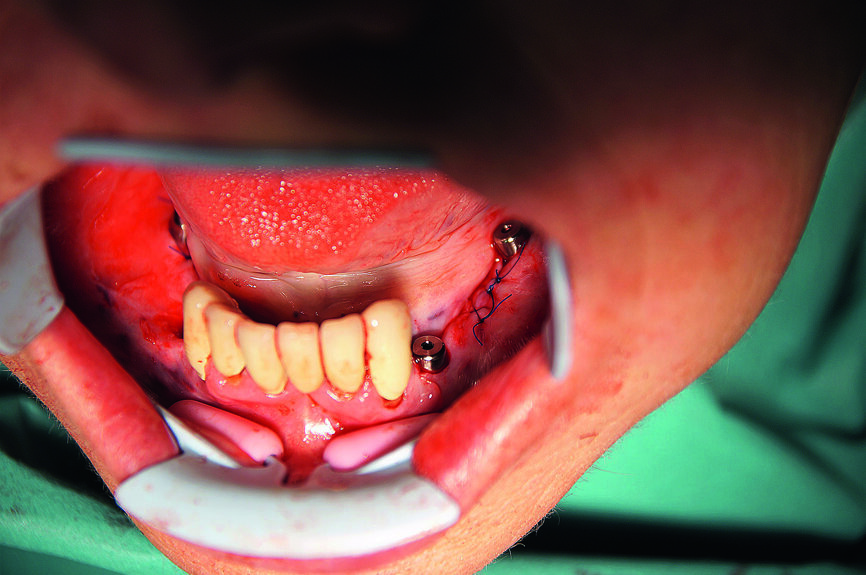

Le guide chirurgical a été correctement positionné dans la cavité buccale par rapport à l’arcade antagoniste. Une attention particulière a été apportée à la mise en place du guide chirurgical (Fig. 7). Après son positionnement correct et sa stabilisation, la chirurgie implantaire sans lambeau a été réalisée conformément au protocole de forage établi pour le type d’implant utilise (Fig. 8). Deux implants CAMLOG de 4,3 mm de diamètre et 13,0 mm de longueur ont été insères selon une technique totalement guidée au niveau des sites dentaires 34 et 44, et des implants de 4,3 mm de diamètre et de 11,0 mm de longueur au niveau des sites dentaires 36 et 46.

Deux petits lambeaux de pleine épaisseur ont également été décollés afin d’éliminer la vis d’ostéosynthèse utilisée pour stabiliser la greffe osseuse autologue de la chirurgie d’augmentation précédente (Fig. 9). L’insertion des implants a été réalisée à l’aide d’une clé à cliquet DRM et d’une douille standard, avec un couple de serrage prédéfini de 35–45 Ncm, afin de parvenir à une stabilité primaire maximale. Les façonneurs gingivaux ont été insérés avec un couple de serrage de 20 Ncm (Fig. 10) et, après l’insertion des implants, les lambeaux ont été suturés au moyen de fils non résorbables (Prolene 5/0). Les sutures ont été retirées après sept jours. Une tomographie panoramique dentaire postopératoire a permis de visualiser les implants insérés dans la mandibule. Les zones d’augmentation osseuse étaient également clairement reconnaissables sur les deux cotés (Fig. 11).

Fig. 15 : Mandibule perforée et préparée.

Fig. 16 : Pose des implants.

Fig. 17 : Insertion manuelle de l’implant CAMLOG au moyen de la clé dynamométrique verrouillée.

Fig. 18 : Tous les implants CAMLOG guidés dans la mandibule.

19 : Résultat de l’implantation avec tous les implants in situ.